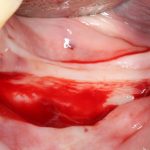

При горизонтальной остеотомии (вертикальной аугментации) очень удобен вестибулярный разрез по переходной складке или чуть ниже:

При вертикальной остеотомии (горизонтальной аугментации), наоборот, разрез делается по вершине альвеолярного гребня. При этом, «послабляющие» дополнительные разрезы не нужны.